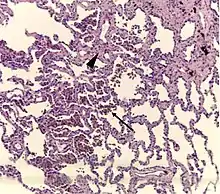

Histopathology of respiratory bronchiolitis: Smoker's macrophages (arrow); mild interstitial lymphocytic infiltrate and mild fibrosis (arrowhead)[2]

Respiratory bronchiolitis is a lung disease associated with tobacco smoking.[1] In pathology, it is defined by the presence of "smoker's macrophages".[1] When manifesting significant clinical symptoms it is referred to as respiratory bronchiolitis interstitial lung disease (RB-ILD).[1]